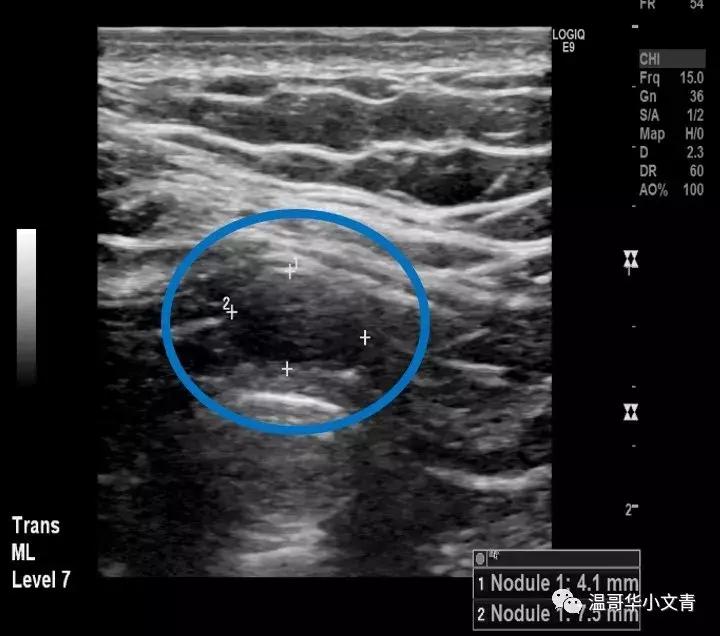

第二个图是一个术前发现的气管前可疑淋巴结,淋巴结长径是8毫米。这个淋巴结也是比较圆,而且内部还能看到一些小的囊性化的成分,基本证明了这是一个转移淋巴结,术后病理显示这个淋巴结里的转移灶是8毫米。

第三个图是一个术前发现的气管旁甲状腺下方可疑淋巴结,淋巴结长径是4毫米。在这个淋巴结中间你能看到明显的钙化,基本证明了这是一个转移淋巴结,术后病理显示这个淋巴结里的转移灶是2毫米。